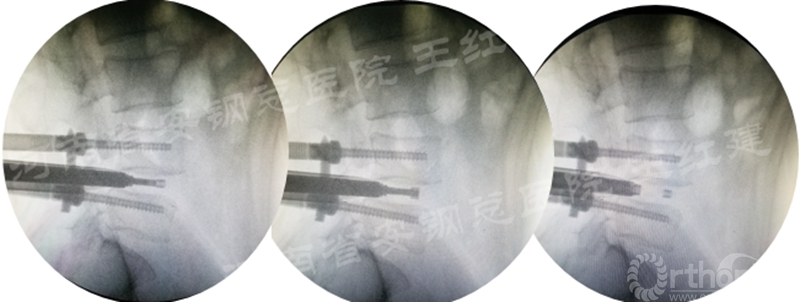

四、经皮螺钉技术固定

在固定的步骤可以先期进行经皮螺钉置入,再进行融合器的置入,进而实现充分固定。

椎弓根植入加压固定

单边椎弓根植入加压固定

双侧椎弓根植入加压固定

手术步骤:先期经皮螺钉置入、再进行融合器的置入